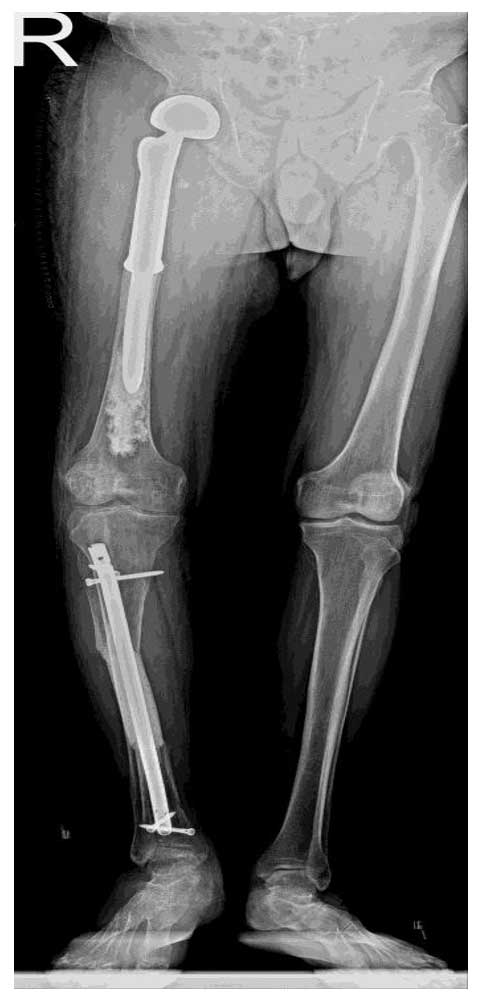

Ameliyat Sonrası: Röntgende sağ femur üst uca uygulanan çimentolu tümör protezi ve tibia’da çimentolama ve kapalı çivileme işlemi görülmekte.